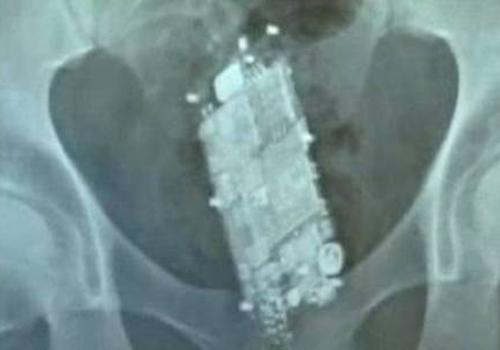

Chapa do raio-x mostra o celular no corpo do detento | Foto: reprodução

A dupla introduziu a bateria e o celular com a ajuda de uma proteção plástica. Os presos tiveram que passar por um procedimento médico para retirada das peças do telefone. A chapa do exame de raio-x mostra o celular dentro do corpo de um deles. Em outra imagem, é possível ver a bateria do telefone que estava com outro detento.